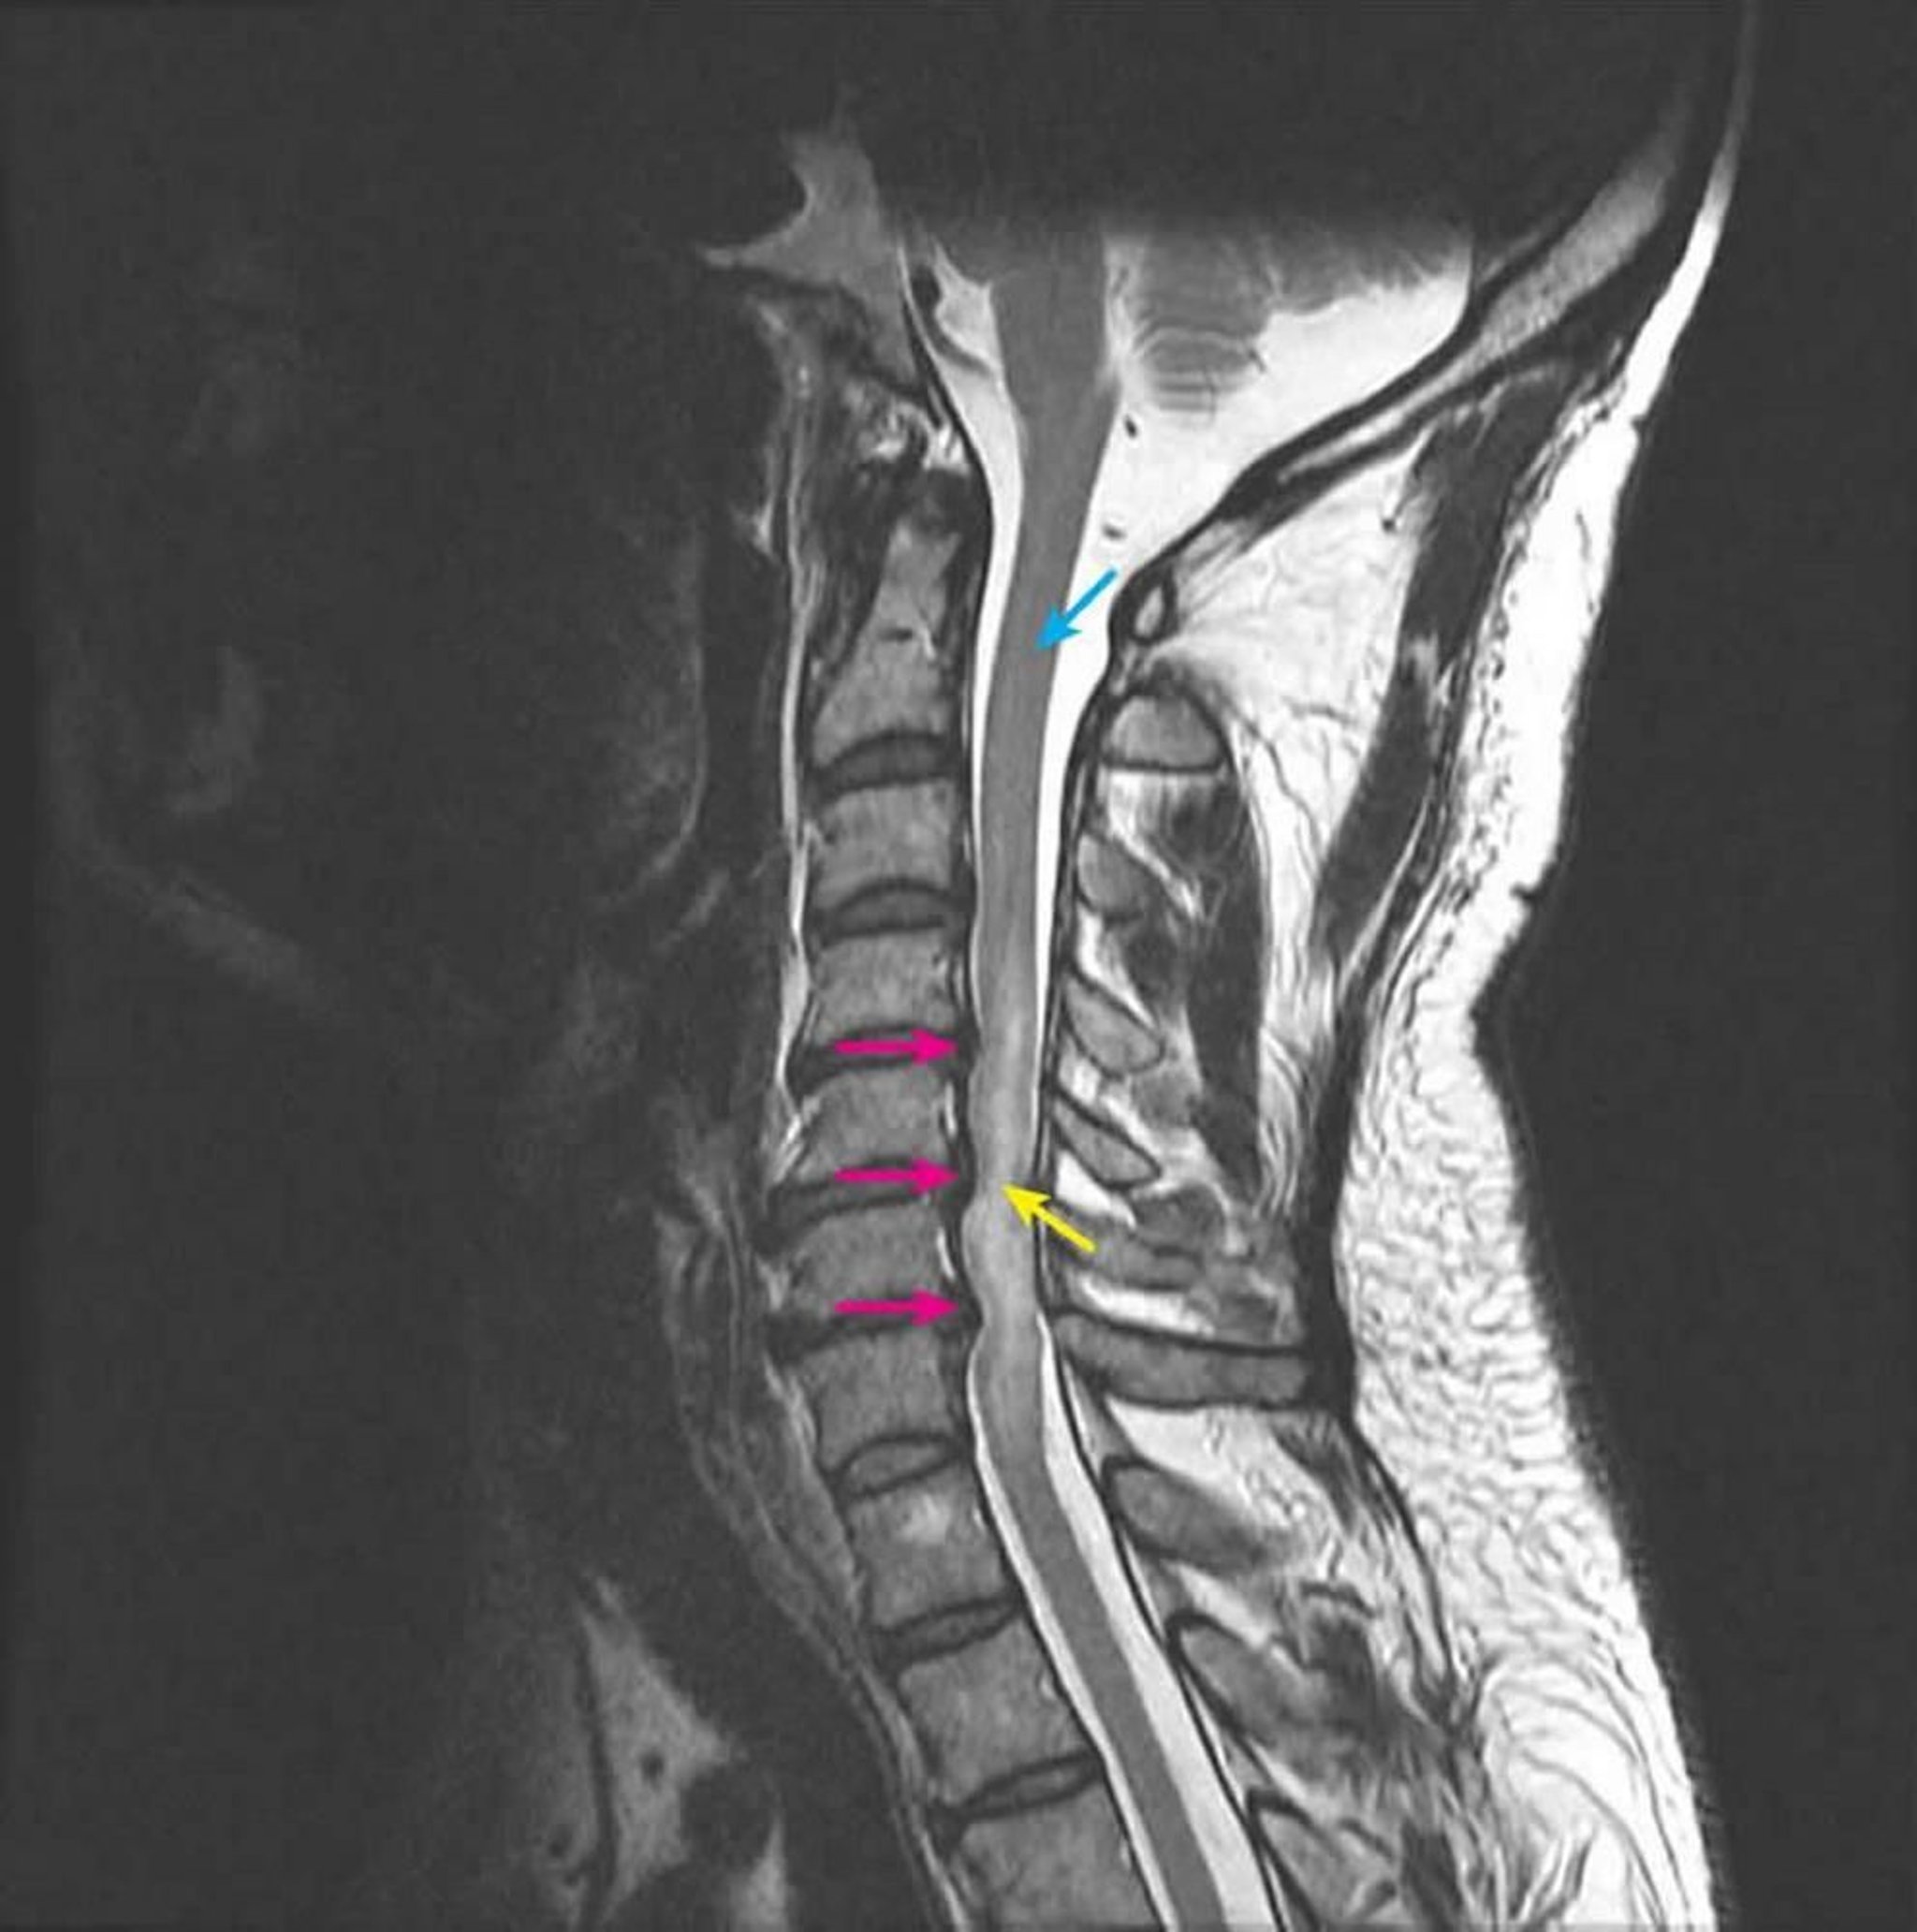

Kompressive Myelopathie

Die sagittale T2-gewichtete MRT zeigt eine Kompression des Rückenmarks auf den Zwischenwirbel-Ebenen C4-5, C5-6 und C6-7 infolge mehrerer posteriorer Bandscheibenvorfälle (rosa Pfeile). Das intramedulläre T2-Signal ist abnorm erhöht, was ein Rückenmarksödem darstellt (gelber Pfeil). Das normale Rückenmarkssignal ist auf der Ebene C2 zu sehen (blauer Pfeil).

Courtesy of John Tsiouris, MD, Division of Neuroradiology, New York–Presbyterian Hospital/Weill Cornell Medical Center.